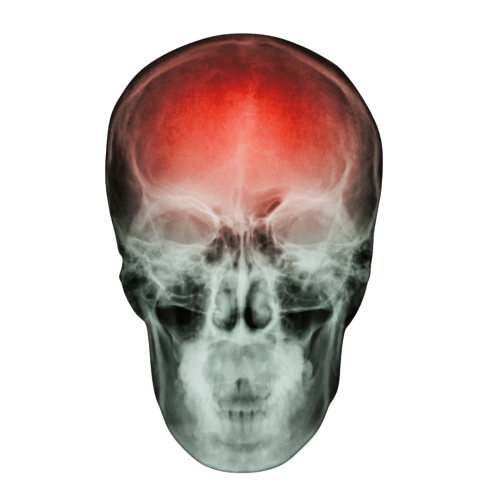

Cada año, millones de personas en el mundo enfrentan las secuelas de un accidente cerebrovascular (ACV), una de las principales causas de discapacidad neurológica. Según la Organización Mundial de la Salud (OMS, 2024), cerca del 40% de la población mundial vive con alguna afección neurológica, y en Ecuador, la comorbilidad asociada ha aumentado un 20% en los últimos años. A pesar de su impacto, hoy sabemos que la recuperación es posible gracias a la neuroplasticidad, la capacidad del cerebro para reorganizarse y crear nuevas conexiones.

¿Qué es un ACV y cómo afecta al cuerpo?

Un accidente cerebrovascular ocurre cuando el flujo sanguíneo hacia una parte del cerebro se interrumpe —ya sea por una obstrucción (isquemia) o por una ruptura de un vaso sanguíneo (hemorragia).

Como consecuencia, las funciones motoras, cognitivas y sensoriales pueden verse afectadas, limitando actividades cotidianas como vestirse, alimentarse o trabajar.